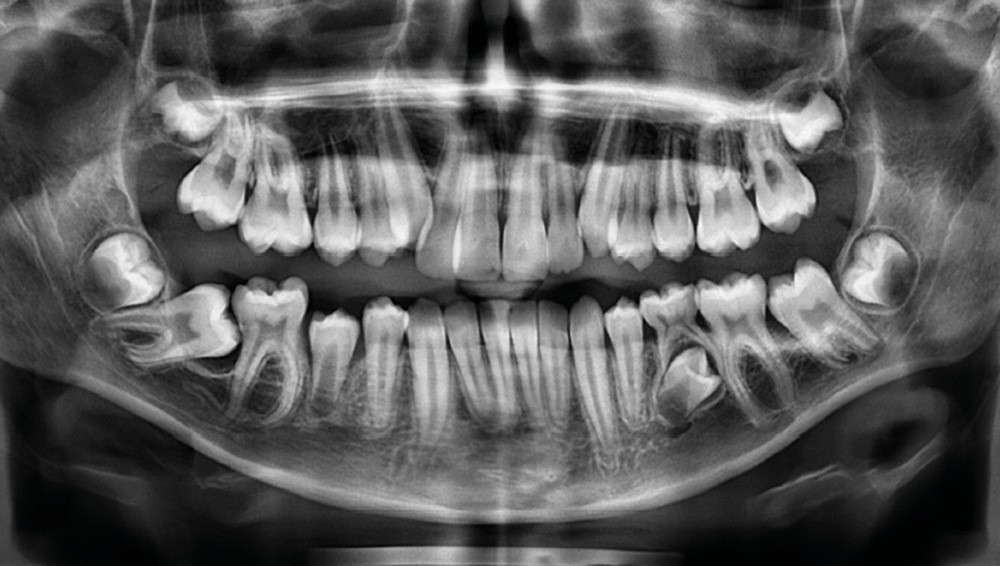

Julien nous consulte à l’âge de 11 ans et 4 mois pour des raisons essentiellement esthétiques, afin d’améliorer l’alignement de ses incisives maxillaires (fig. 1a-d) ; son chirurgien-dentiste l’a toutefois alerté sur un problème d’évolution des 35 et 47, dont l’inclusion a été mise en évidence lors d’un contrôle radiographique (fig. 1e).

L’examen intra-oral met en évidence une occlusion inversée bilatérale ainsi qu’un manque de place conséquent pour les incisives latérales maxillaires en palato-position et une infra-vestibulo-position de 13 et 23. Le patient est déjà en denture adulte jeune, hormis la persistance de la 75. L’occlusion est en classe II, plus marquée du côté droit sans engendrer de déviation des médianes incisives, d’où une mésio-position plus importante de la 13 par rapport à la 23.